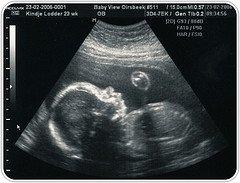

Algunas personas parecen insistir en que lo que hace referencia al derecho a la vida – que incluye el derecho a vivir de los concebidos y aún no nacidos - forma parte de la ética individual, sin apenas repercusiones sociales. Según este criterio, en un momento de grave crisis económica no se podría hablar, por ejemplo, de la inmoralidad del aborto.

Entre persona y sociedad no existe un hiato. El ser humano es un ser social y la persona humana se abre al tú y al nosotros. A su vez, la sociedad solo puede edificarse sobre bases justas si todos los derechos – y, entre ellos, el más elemental de todos, el derecho a vivir – son protegidos y custodiados.